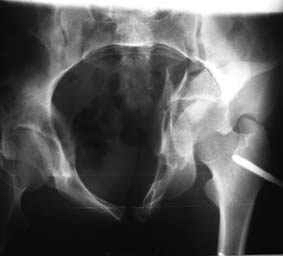

Уважаемые коллеги! Хотелось бы услышать совет по тактике лечения представлленого больного.Поступил после лечения в одном изотделений области. Травма 2,5 месяца назад. После выведенияиз шока был произведен остеосинтез перелома бедра, предплечья, до перевода к нам проводилосьвытяжение по оси шейки бедра за стержень, введенный в большой вертел. На сегодня деформацияригидна, клинически мобильности не определяется. Заранее признателен. P.S. Данный вид травм не включен в перечень "высокотехнологичных операций", направить длялечения по квотам Минздрава очень сложно.

Это обзорные и косые снимки

Привет, Леонид. Оскольчатый высокий двухколонный перелом в такие сроки трогать не надо, т.к. это про такие переломы сказано: "кто с ножом на Ж. пойдет тот в ней и останется...".